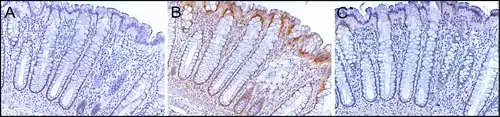

PMS2 is usually expressed at a high level in cell nuclei of enterocytes (absorptive cells) within the colonic crypts lining the inner surface of the colon (see image, panel A). DNA repair, involving high expression of PMS2, ERCC1 and ERCC4 (XPF) proteins, appears to be very active in colon crypts in normal, non-neoplastic colonic epithelium. In the case of PMS2, the expression level in normal colonic epithelium is high in 77% to 100% of crypts.[27]

Cells are produced at the crypt base and migrate upward along the crypt axis before being shed into the colonic lumen days later.[28] There are 5 to 6 stem cells at the bases of the crypts.[28] If the stem cells at the base of the crypt express PMS2, generally all several thousand cells of the crypt[29] will also express PMS2. This is indicated by the brown color seen by immunostaining of PMS2 in most of the enterocytes in the crypt in panel A of the image in this section. Similar expression of ERCC4 (XPF) and ERCC1 occurs in the thousands of enterocytes in each colonic crypt of the normal colonic epithelium.

The tissue section in the image shown here was also counterstained with hematoxylin to stain DNA in nuclei a blue-gray color. Nuclei of cells in the lamina propria (cells which are below and surround the epithelial crypts) largely show hematoxylin blue-gray color and have little expression of PMS2, ERCC1 or ERCC4 (XPF).